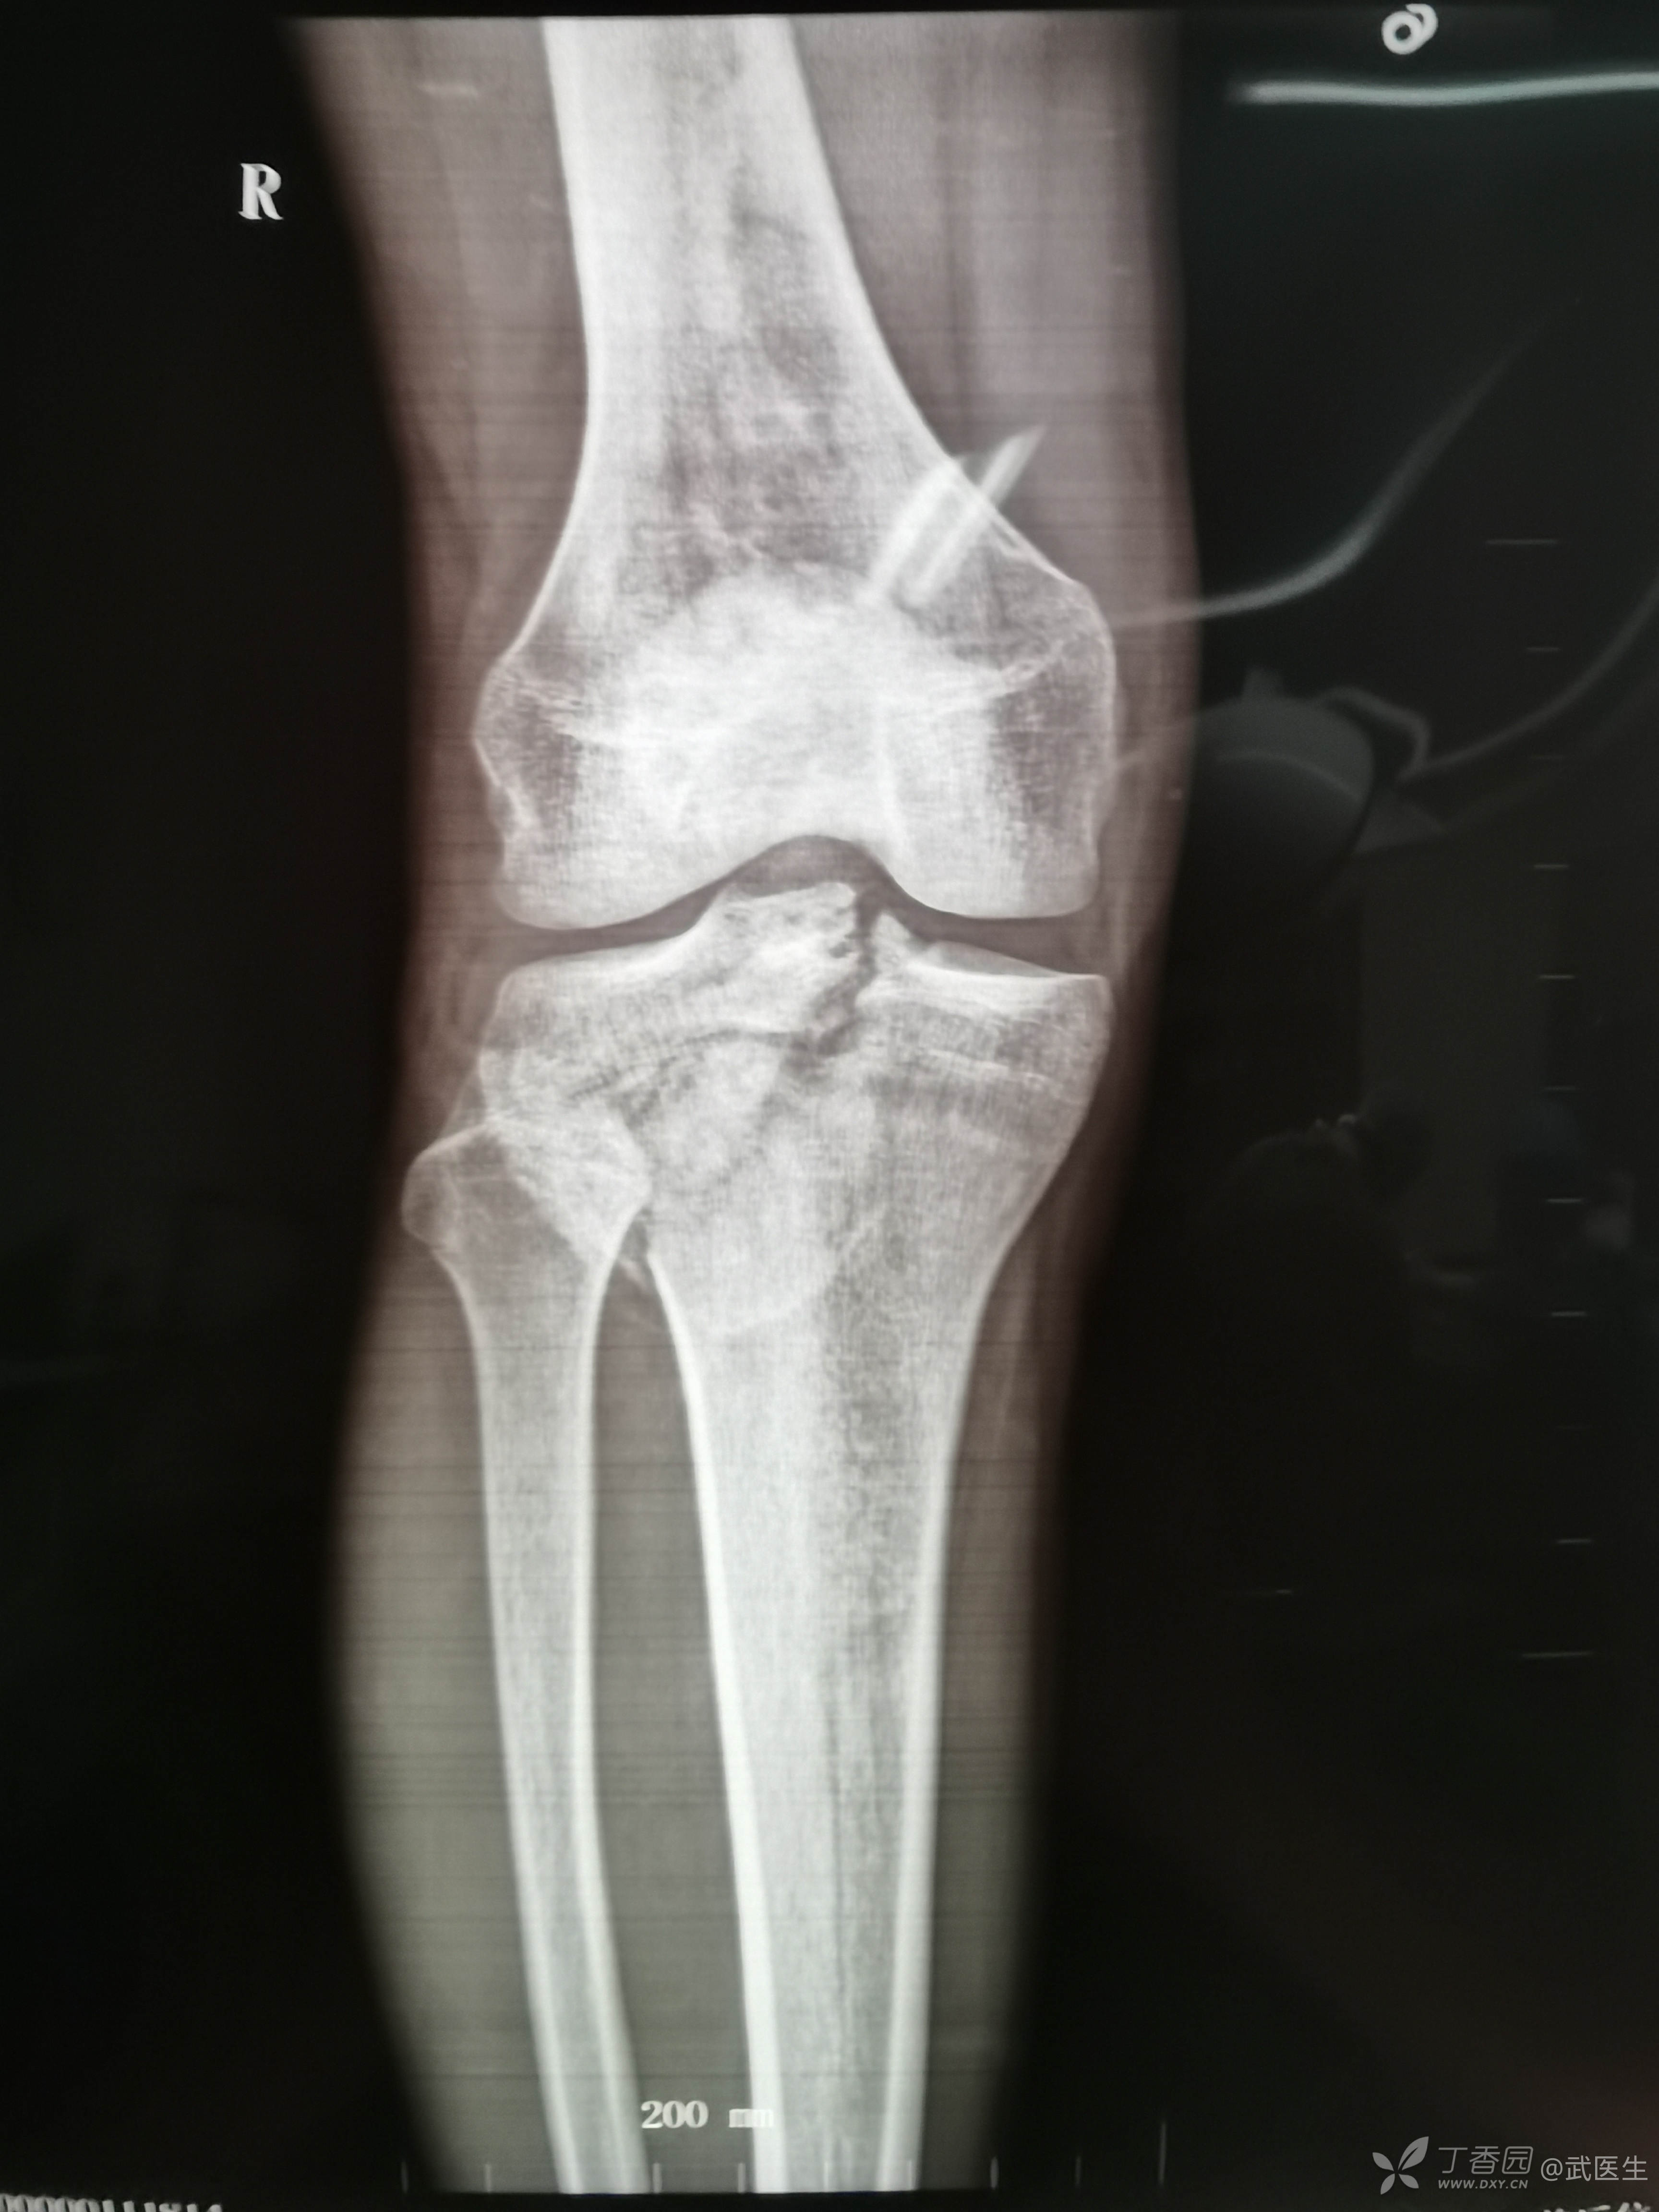

男,15岁,骑摩托车摔伤致右膝疼痛,出血,活动受限三小时就诊,门诊诊断“右胫骨平台骨折,右膝挫裂伤”急诊入院,片子如下,受伤体位照缺失